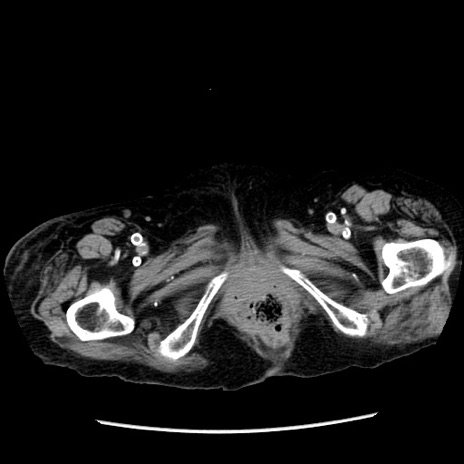

症例14(横断像)

【症例】 90歳代女性

【主訴】 腹痛・嘔吐

【現病歴】今朝から左側腹部痛を認めた。 経過観察していたが、嘔吐を認めたため来院。

【既往歴】 子宮癌術後

【身体所見】 意識清明、BP 127/54mmHg、P 98bpm Sp02 95%(RA)、BT 35.8°C、腹部平坦・軟腸ぜん動音聴取良好、右下腹部圧痛(+) 反跳痛なし

【データ】WBC 9800、CRP 0.46